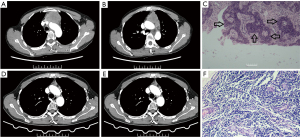

A 39-year-old male patient was admitted to The Third Affiliated Hospital of Chongqing Medical University with a 1-year history of left-sided intermittent chest pain, which worsened over the course of 2 months. The patient showed no ocular or limb weakness, dysphagia, or dyspnea, and denied any family history of thymic tumor (Table 1). A chest computed tomography (CT) scan revealed a left anterior superior mediastinal tumor measuring 72 mm × 67 mm in size, characterized by uneven density and significant enhancement. The tumor exhibited a close association with the ascending aorta and pulmonary artery, as well as a filling defect in the left cephalic and brachial veins. The presence of liver metastasis was also detected. The classification is stage IV according to the Masaoka-Koga staging system that precluded direct surgical intervention. CT-guided puncture biopsy pathology confirmed the diagnosis of low-differentiated squamous carcinoma with a PD-L1 tumor proportion score (TPS) of 75%. Following treatment with a combination of PD-1 checkpoint inhibitors (sintilimab 200 mg) albumin-bound paclitaxel (240 mg/m2) and carboplatin [area under the curve (AUC) =5] over a period of 4 cycles, subsequent CT examination demonstrated tumor regression to a size of 44 mm × 36 mm. Furthermore, the relationship between the tumor and the ascending aorta, pulmonary artery, and the left cephalic and brachial veins was more clearly defined compared to previous observations (Table 2). In accordance with the Response Evaluation Criteria in Solid Tumors (RECIST) version 1.1 guidelines, the therapeutic outcome has been classified as Partial Response (14). Positron emission tomography (PET)-CT assessment confirmed the active status of the tumor, with no discernible metastases aside from the liver lesion. Following extensive interdisciplinary deliberation, the patient underwent tumor regression treatment, with a complete excision procedure anticipated. Subsequent to obtaining informed consent, a central sternotomy was performed. Throughout the surgical procedure, it was observed that the tumor exhibited close proximity to the pulmonary artery and the aorta, yet it remained amenable to separation. Additionally, the tumor was found to have infiltrated the pericardium encompassing the excision of the mediastinal tumor and partial pericardial resection. Postoperative histopathology revealed fibrous tissue hyperplasia within the mediastinal tissue accompanied by the presence of cholesterol crystals and significant infiltration of inflammatory cells. Locally, a substantial presence of foam cells was observed, while malignant cells were conspicuously absent. Consequently, the patient achieved a comprehensive pathological remission (Figure 1). The patient underwent two cycles of sintilimab as adjuvant therapy following the surgical procedure. Subsequent follow-up evaluations at 3, 6, and 12 months post-surgery, using enhanced CT scans of the chest, showed no evidence of tumor recurrence or metastasis (Figure 2). The patient experienced a number of adverse reactions subsequent to medication, including alopecia, nausea, and arthralgia, which were plausibly associated with the administration of chemotherapeutic agents. Furthermore, transient immune-mediated hepatitis developed subsequent to the initial drug cycle, primarily manifesting as elevated levels of bilirubin (indirect bilirubin: 12.0 µmol/L, ref. value 1.7–10.2 µmol/L). In accordance with guidelines for managing irAEs associated with ICIs, this adverse reaction was classified as grade I (15). The patient experienced complete recovery upon receiving hepatoprotective treatment, displaying no recurrence during subsequent therapeutic intervention. Furthermore, a transient case of immune-related myocardial injury was observed, manifesting as a mild elevation in cardiac troponin I levels (cardiac troponin I 0.187 ng/mL, ref. value 0–0.03 ng/mL), with electrocardiographic findings remaining unremarkable. Following treatment, the patient’s cardiac troponin I levels returned to normal and did not exhibit subsequent elevation, negating any impact of the use of PD-1 inhibitors. Additionally, transient hyperthyroidism was evident in the form of a slight elevation in serum T4 levels (total thyroxine T4 156.78 nmol/L, ref. value 73.74–137.15 nmol/L), which spontaneously resolved without therapeutic intervention (Table 3).

A 52-year-old female patient was admitted to The Third Affiliated Hospital of Chongqing Medical University with a mediastinal tumor that had been detected on a CT scan 6 days prior. She did not exhibit any ocular or generalized muscle weakness and had no familial history of thymic tumors (Table 1). The chest CT scan revealed a left anterior superior mediastinal tumor 57 mm × 58 mm in size with slight enhancement that was infiltrating the pericardium, left subclavian artery, left innominate vein, and thoracic aorta. The classification is stage III according to the Masaoka-Koga staging system, indicating that direct surgical resection of the mediastinal tumor was not feasible. Puncture biopsy pathology identified the tumor as low-grade squamous carcinoma with a PD-L1 TPS of 85%. Following 4 cycles of Albumin-bound paclitaxel (240 mg/m2) combined with carboplatin (AUC =5) with sintilimab (200 mg), a CT scan demonstrated tumor reduction to a size of 11 mm × 28 mm, with improved demarcation from the peripheral arteries and pericardium (Table 2). In accordance with the RECIST version 1.1 guidelines, the therapeutic outcome has been classified as partial response. After a multidisciplinary discussion, the treatment plan devised involved achieving tumor shrinkage with the intention of complete resection. The patient consented and subsequently underwent a median sternotomy for mediastinal tumor resection partial pericardiectomy, and partial removal of the left innominate vein, because it was found that the tumor invaded the left innominate vein and the pericardium. Postoperative pathological analysis revealed chronic inflammatory cell infiltration with necrosis in the mediastinal tumor tissue, displaying complete pathological remission (Figure 3). The patient underwent two cycles of sintilimab as adjuvant therapy following the surgical procedure (Figure 4). During the 3-, 6-, and 12-month postoperative follow-ups, enhanced CT scan of the chest showed no tumor recurrence or metastasis. The patient experienced chemotherapy-related adverse reactions, including alopecia, nausea, and arthralgia. Additionally, the patient encountered transient immune-related hepatitis after the first cycle, primarily manifesting as a mild elevation in Alanine transaminase levels (ref. value 7.0–40.0 U/L). However, with appropriate hepatoprotective treatment, liver function returned to normal and subsequent treatment, including the use of PD-1 inhibitors, was unaffected (Table 3).